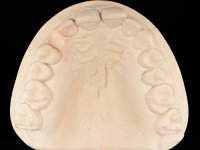

To define the dental zone to be covered by the Maryland bridge retainers, the patient was asked to perform maximum intercuspidation movements, and the contact points were marked with articular paper. Tooth preparation of the interproximal surfaces was made, to create a prosthetic insertion axis. It was sought that the mesio-distal diameter at the incisal level was equal to the diameter mesio-distal at the cervical level, that is to say, the interproximal walls were parallelized. Tooth preparation was done with fine grain diamond drills, and later polishing was done with abrasive discs. Color information was collected even before confection of the impression, to avoid dehydration of the arcade. Definitive impression was made using wash technique impression with silicone of heavy and regular consistency, both with fast setting, and a working plaster model was prepared in the lab. A laboratory scanner was used to scan the working model, and later, the infrastructure for the Maryland bridge was made using a CAD-CAM process. Ceramic was placed on this subframe. A ceramic adhesive was applied to the internal surface of the wings and connectors, which would enable bonding to the adjacent teeth. The adhesive bridge was bonded in the mouth following the conventional bonding technique. After bonding, the protrusion and laterality movements were carefully checked to avoid undesirable contacts.